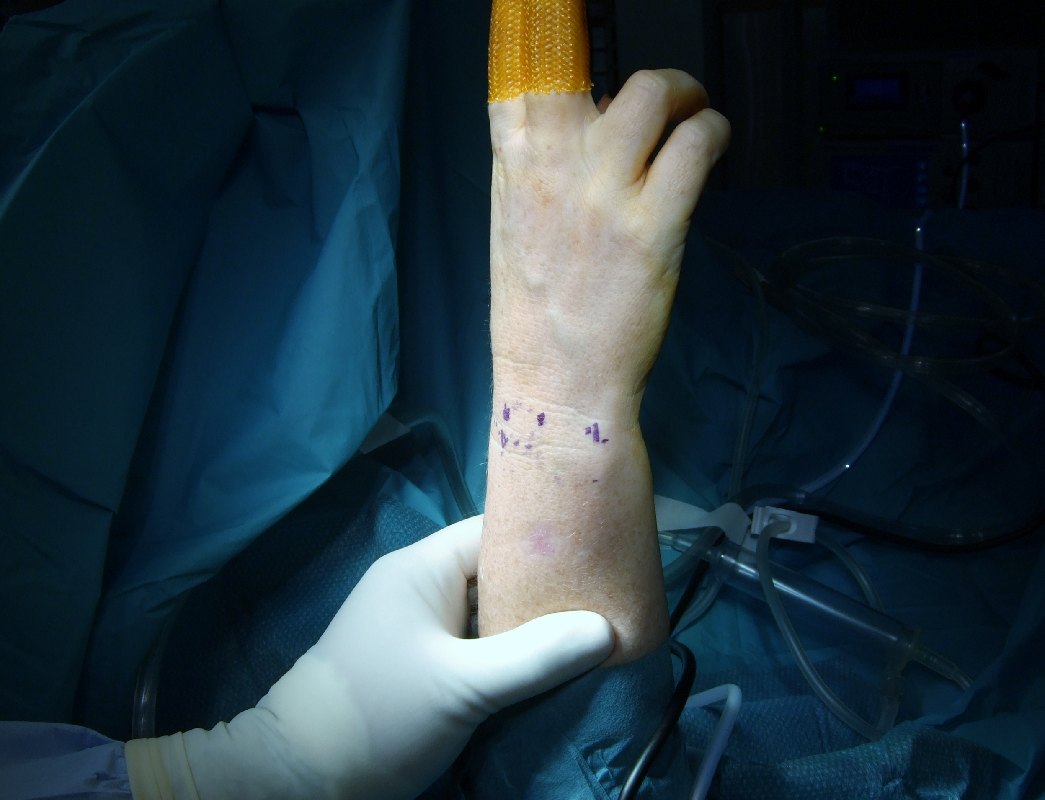

- 2 to 3 Small Incisions at the Wrist level

- Wrist arthroscopy under regional block.

- Right Hand and Wrist was suspended with 8 lbs of traction.